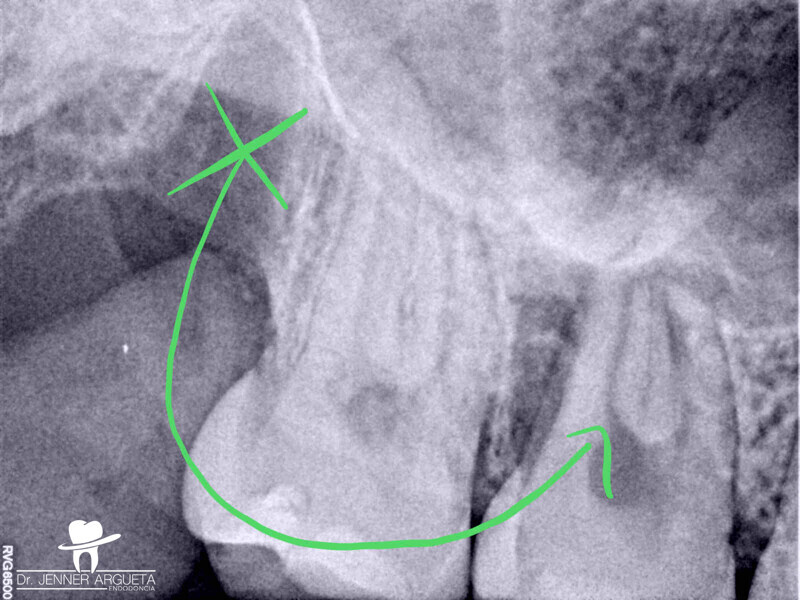

Autogenous transplantation followed by conservative root canal therapy: Three years follow-up